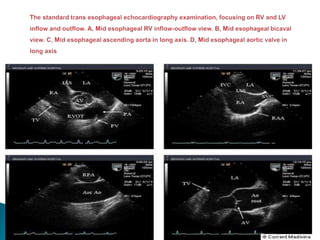

 0 Degree(transverse Plane)- Oblique view of upper esophageal

basal structures, the mid esophageal four chamber view or basal

transgastric short axis view can be obtained from this position by

reteroflexion and Anteflexion of transducer tip.

 45 Degrees- Short axis view of the aortic valve

 90 Degrees- Longitudinal transducer orientation, produce

images oblique to the long axis of the heart.

 135 Degrees- True long axis of the LA and left ventricular

outflow tract(LVOT)

With transducer array at 90 degrees, the plane is Sagittal to the

body and oblique to the long axis of the Heart.

1. Counterclockwise rotation of the probe-two chamber left

ventricular inflow view

2. Slight clockwise rotation of probe from first view, produce long axis

of right ventricular outflow tract(RVOT)

3.Further clockwise rotation-Long axis view of proximal

ascending aorta.

4.Further clockwise rotation-Long axis view of the Vena

Cava and Atrial septum.